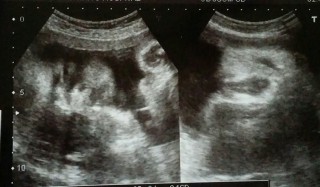

2110gの可愛い女の子。やっと2000gを超えてくれました! こっちを向いて右手を顔の前にやっています。今日は瞬きをしているところを見られました^^そして、なんと笑ってました!! 先生が、『笑ってこっち見てるねぇ。あ、瞬きした!』って^^ 右のエコーは女の子マークです♪ 週数の割には少し小さめですが、元気いっぱいだと聞いて安心しました。

2200gの男の子です!左側にあるのは手だそう。今までなかなかお顔が撮れなかったのですが、ようやくばっちり見せてくれて嬉しかったです☆

35週1日4Dエコーの写真です。胎児がかなり人間の顔をしていて驚きました。どう見ても小さい私の顔です(笑)携帯で写真を撮った時、胎児の顔を携帯が顔認識していてビックリしました!人認定されてます!(笑)